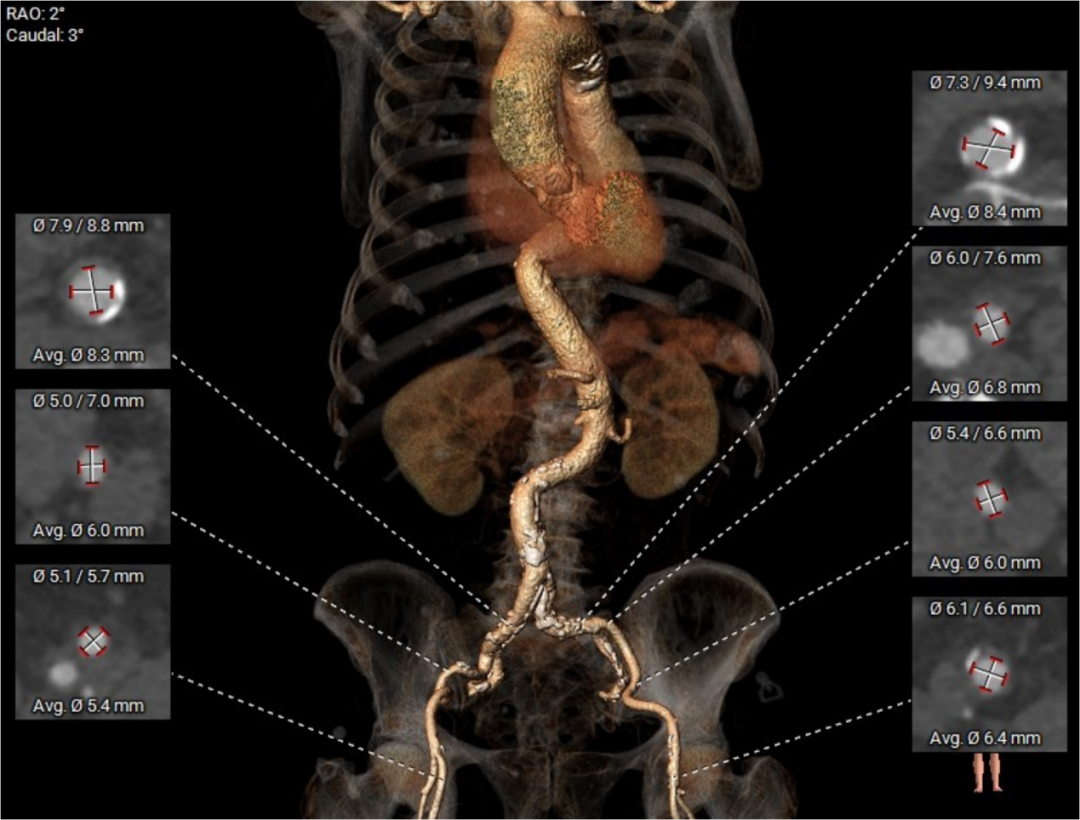

主动脉根部评估

四叶式主动脉瓣,右无间窦体发育较小且窦底高于瓣环平面约6mm;

AAO轻度扩张,Max>43.1;

瓣环上结构测量

收缩期瓣上结构

收缩期瓣上可提供4~6mm筒状区域。

舒张期瓣上结构

舒张期瓣上5mm内区域均小于收缩瓣环径;

该病例的瓣上结构可提供的辅助锚定区域较长,有利于瓣膜的辅助锚定。

流出道结构测量

收缩期流出道结构

收缩期流出道可提供6mm筒状区域。

舒张期流出道结构

舒张期流出道约3mm筒状区域;

流出道收缩期和舒张期可锚定区域波动较大,整体约4mm辅助锚定区域。

冠脉高度、瓣叶长度及左室内径

左冠高度:7.1mm;右冠高度:13.4mm;

左冠-窦底距:9.7mm;右冠-窦底距:14.4mm;

左冠瓣长度:12.3mm;右冠瓣长度:14.8mm;

左冠水平高度较低,开口内径较大,瓣叶略长,LCC至对合缘距离约30mm,存在一定左冠阻塞风险。

左室室间隔基底部肌性凸起,增加了流出道锚定有利因素。

外周血管及主动脉弓形态

右侧股动脉分叉较高,考虑本中心常规采用切开游离方式,选择左侧主入路。